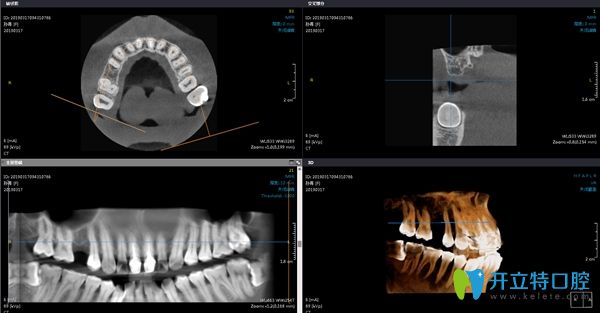

在術前進行常規(guī)的檢查,拍片對骨質量進行測量及評估,確定擬植入種植體的規(guī)格。